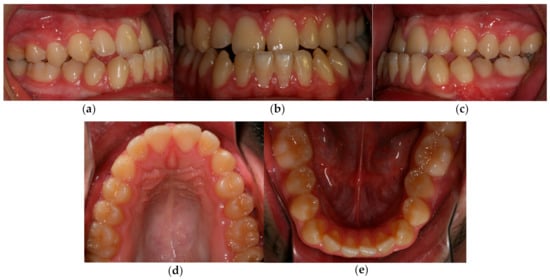

3.4. Treatment Results